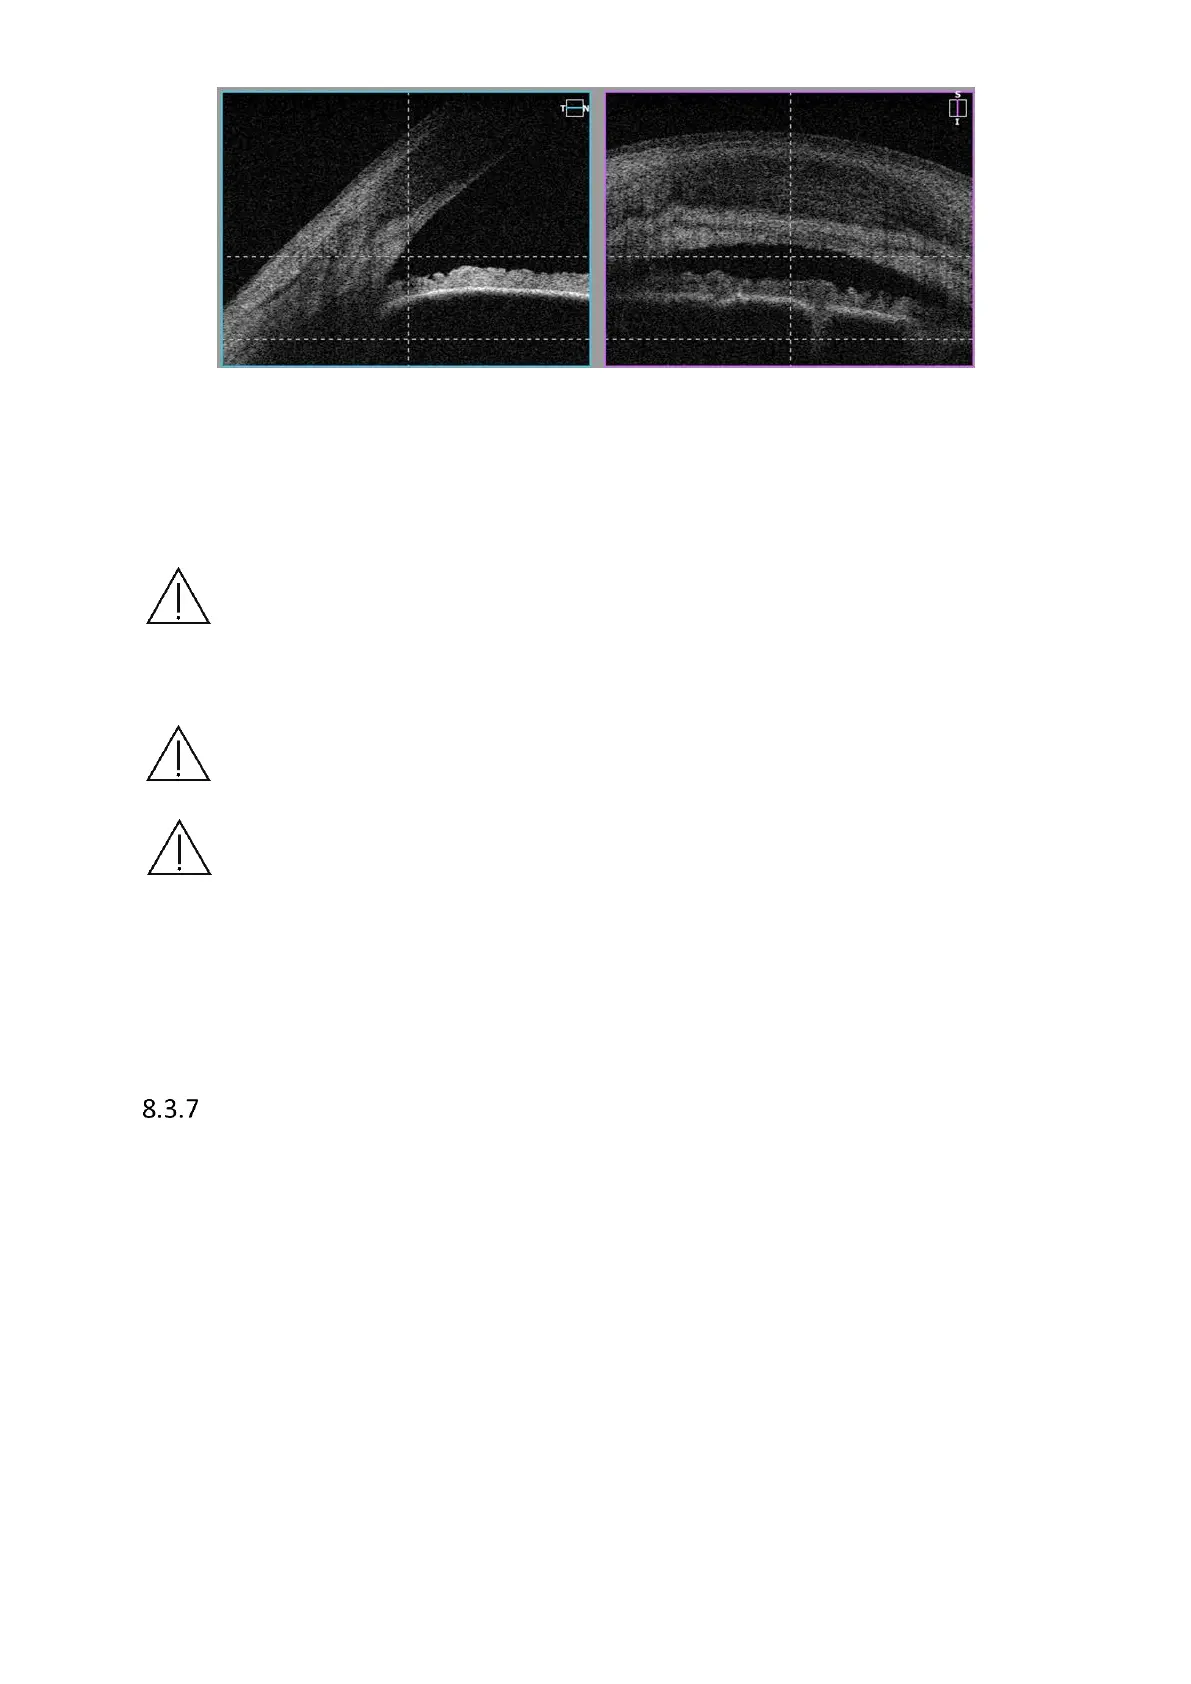

Figure 46.Single angle measurement proper alignment

5) Once the scan location is set in selected place, click twice on the tomogram or press

[Acquire] button. PC will initialize measurement process and then full scan will be

performed.

NOTE: Only when border air - anterior surface is correct are AOD and TISA

measurements accurate. Verify recognition correction before judging the Anterior

Angle morphology.

NOTE: Vertical dense line in the center of Cornea is a natural reflection of laser light

and has no negative influence on measurement result. It can be used to locate the

tomogram in proper position.